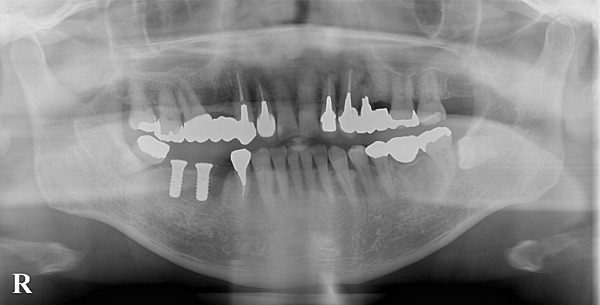

こちらが術後のレントゲン写真になります。

シンプルな処置だったため、術後もほとんど腫れや痛みといった不快症状は出なかったようです。

インプラントと骨がしっかり結合するのを2ヶ月程度待ち、型取りを行いました。